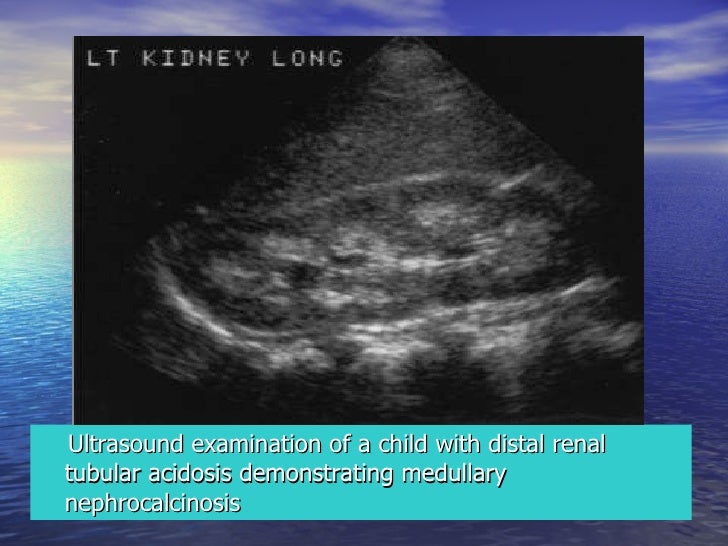

Management of chronic metabolic acidosis associated with chronic renal insufficiency or renal tubular acidosis.Alkalinization of urine.Prevention of cystine and urate urinary calculi.Prevention of aspiration pneumonitis during surgical procedures.Used as a neutralizing buffer. Action